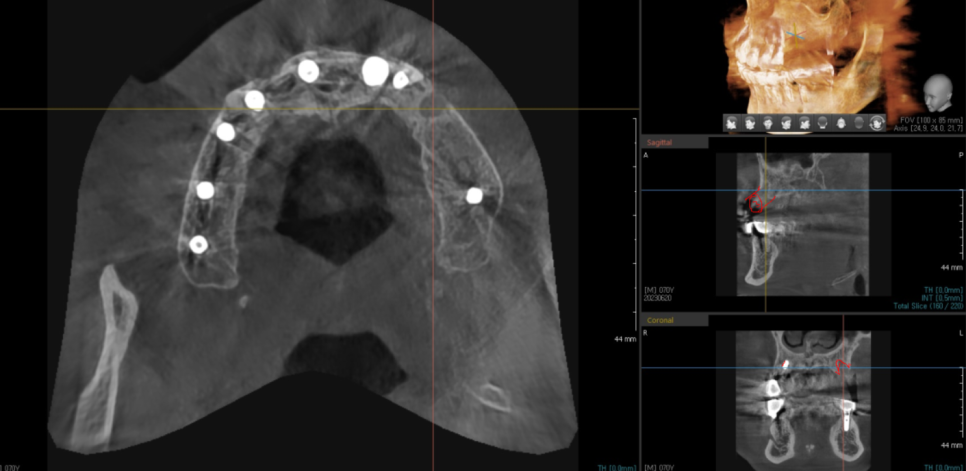

23.08.25

#24,26 임플란트 2개가 들어갔습니다.

예전에는 2개 임플란트에 4개의 어금니를 만들었지만

2개가 4개의 힘을 나눠 했다면

23.11.20

다시 하시는 만큼

3개가 4개의 일을 하도록 하였습니다.

덕풍동 치과에서 튼튼하게 보강하였습니다.

임플란트 치아에 힘을 분배해

부담을 덜어준 것이죠